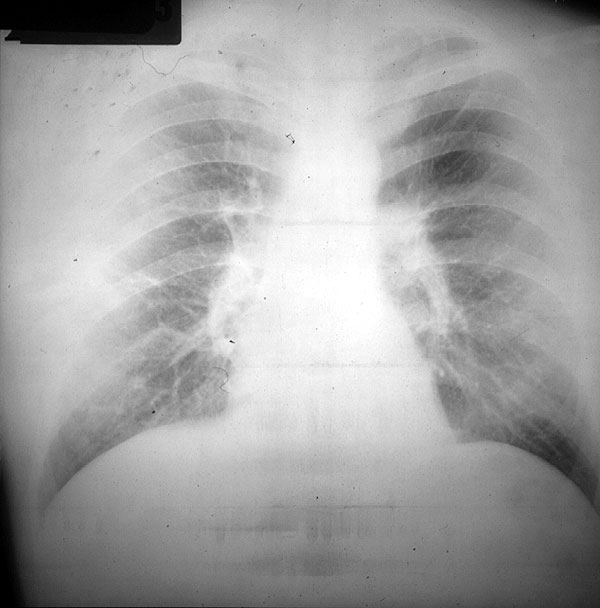

Repita el proceso de comparación con la placa de buena calidad.